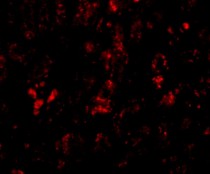

ARG55110 anti-APAP1L2 antibody IHC image

Immunohistochemistry: AFAP1L2 in human liver tissue stained with ARG55110 anti-APAP1L2 antibody at 20 ug/ml dilution.